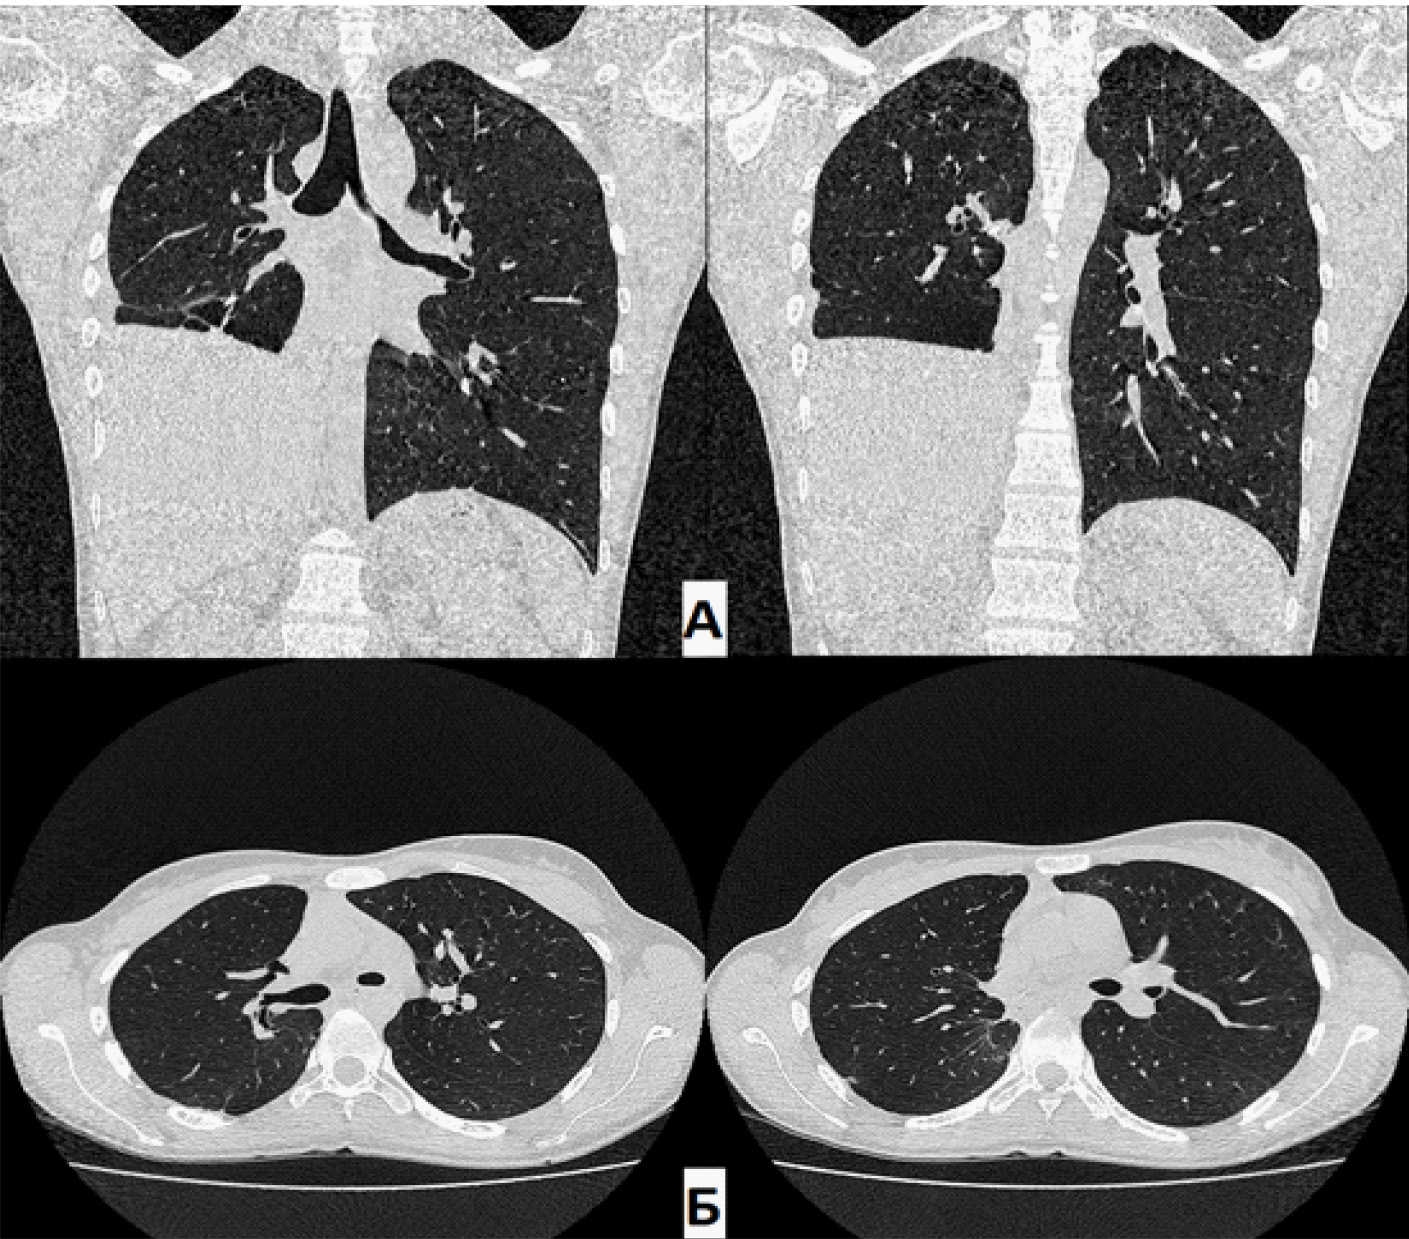

При контрольном КТ ОГК через 3 мес. после операции (28.02.2022): данные за бронхоплевральное сообщение отсутствуют. Пациентка выписана из отделения для продолжения лечения в ПТД по месту жительства.

При контрольном КТ ОГК через 1,5 года: в динамике – полное отсутствие ОПП. Состояние после этапного хирургического лечения. В оставшихся отделах правого легкого без патологических изменений. Эмфизематозные изменения верхней доли правого легкого. Тень средостения располагается срединно, правый купол диафрагмы приподнят до уровня V межреберья.

Рис. 5. Компьютерная томография (А – фронтальная проекция; Б – аксиальная проекция) через 1,5 года. Отсутствие остаточной плевральной полости справа